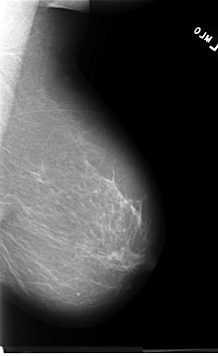

B_3060_1.LEFT_MLO

LEFT_MLO LINES 5688 PIXELS_PER_LINE 3488 BITS_PER_PIXEL 12 RESOLUTION 50 NON_OVERLAY